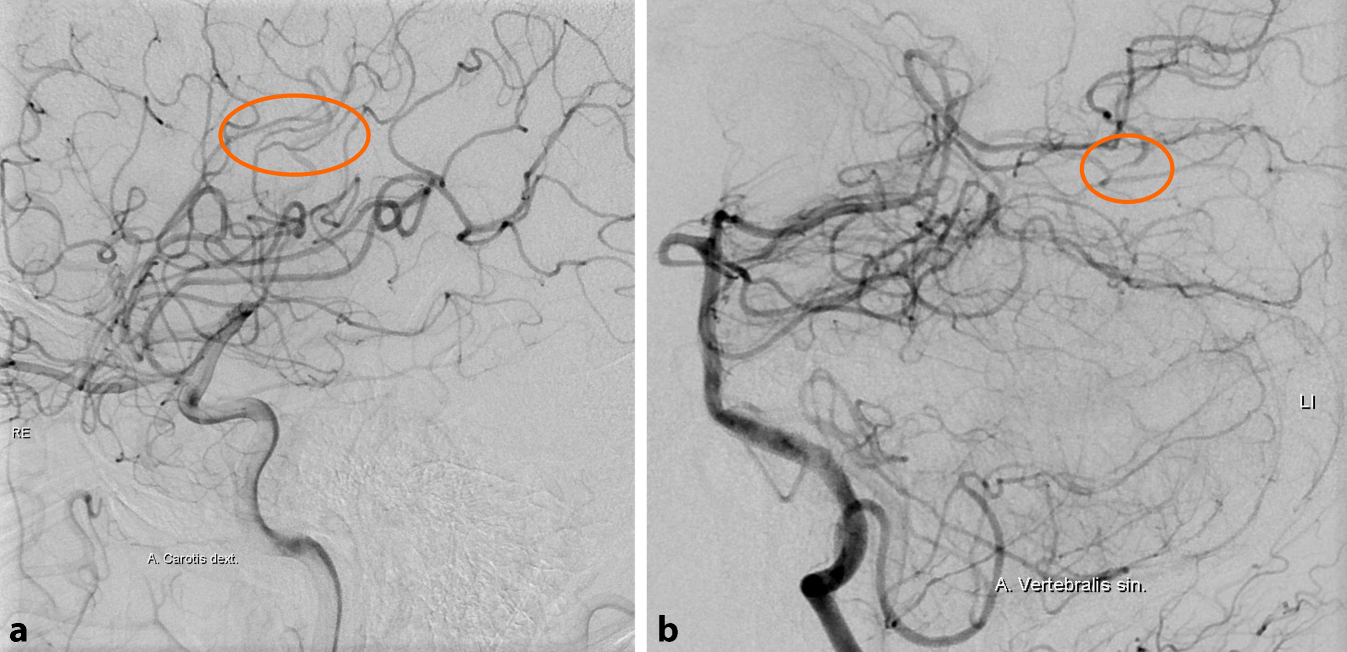

Abb. 1

In FLAIR (Fluid-attenuated Inversion Recovery)-gewichteten MRT-Sequenzen a und b zeigen sich bilaterale supratentorielle Marklagerhyperintensitäten. Die TOF-MRA (Time of Flight Magnetresonanzangiographie) bleibt bis auf ein aplastisches A1-Segment der rechten A. cerebri anterior unauffällig (c). In einer erneuten MRT 2 Tage später kommt nun ein ischämischer Infarkt im paramedianen Pons links zur Darstellung (DWI [Diffusion Weighted Imaging]: f, ADC [Apparent Diffusion Coefficient]: e, Pfeile), welcher sich auch bereits in FLAIR-Sequenzen demarkiert zeigt (f). (© Univ.-Klinik für Radiologie, LKH Univ.-Klinikum Graz)

Ein 34-jähriger Patient stellte sich mit einer transienten, für einige Stunden bestehenden Halbseitenlähmung rechts an der neurologischen Notaufnahme vor. Zusätzlich berichtete der bis dato gesunde Patient über seit ca. 3 Wochen vorhandene Kopfschmerzen sowie ein allgemeines Krankheitsgefühl. In der klinischen Untersuchung zeigte sich eine geringgradige zentrale Fazialisparese rechts. Das Routinelabor war unauffällig. In der MRT des Gehirns fanden sich fleckförmige, teils konfluierende, vorwiegend subkortikal gelegene Marklagerhyperintensitäten in beiden Großhirnhemisphären, welche in erster Linie als mikroangiopathisch beurteilt wurden (Abb. 1a, b). Unter der Annahme einer zerebralen Ischämie wurde ASS eingeleitet und der Patient stationär aufgenommen.

Zwei Tage danach entwickelte er erneut plötzlich eine sensomotorische Halbseitensymptomatik rechts sowie Dysarthrie. In der MRT kam nun ein rezenter ischämischer Infarkt im Pons paramedian links zur Darstellung (Abb. 1d–f). In der MR-Angiographie ergaben sich keine Hinweise für relevante Verschlussprozesse oder Aneurysmata, auch zeigte sich keine pathologische Kontrastmittelaufnahme. Klinisch präsentierte sich die Ausfallsymptomatik über Tage progredient mit Entwicklung einer höhergradigen Hemiparese rechts und ausgeprägter Dysarthrie. In einer weiterführend veranlassten Lumbalpunktion wurde eine lymphomonozytäre Pleozytose (20 Zellen/μl) mit leichter Schrankenfunktionsstörung nachgewiesen, oligoklonale Banden waren negativ. In einer umfassenden Erregerdiagnostik von Blut und Liquor cerebrospinalis (u. a. Bakterien- und Pilzkulturen, Borrelien, Lues, Virologie inkl. HIV und VZV [Varizella Zoster Virus]) fanden sich, wie auch in der transösophagealen Echokardiographie keine auffälligen Befunde. Zyto- sowie molekularpathologisch ergab sich kein Hinweis für Malignität.